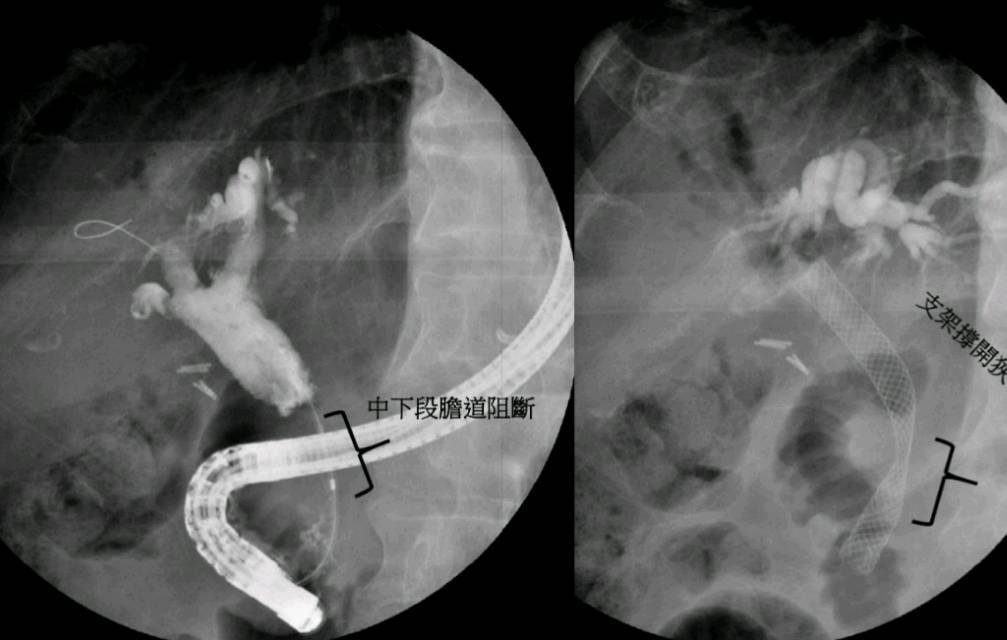

王堯生醫師指出,體內膽管置放支架引流術的優點在於針對中、遠段的膽管阻塞,透過內視鏡及X光透視鏡的輔助,將塑膠或金屬支架置入膽管狹窄處,金屬支架更有自主擴張狹窄處的優勢,與心臟冠狀動脈支架的原理類似。研究顯示金屬支架相較於塑膠支架的使用期間更久,可以減少重複接受內視鏡治療的次數,對惡性腫瘤膽管阻塞的病人有增加存活的時間。

王堯生醫師說明,金屬支架也適用於良性膽管狹窄,更有主動擴張狹窄處的優勢,對於慢性胰臟炎所造成的膽管狹窄,其臨床治療效果更勝於塑膠支架。